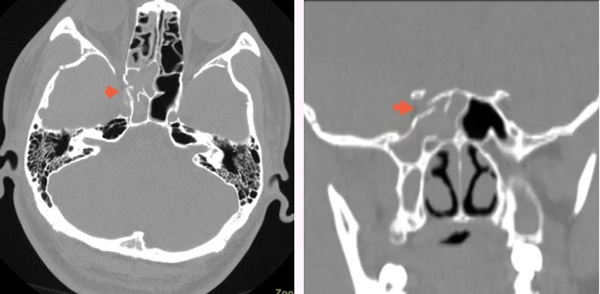

患者男性,23岁,此前骑电动车发生交通事故,右侧头面部受力,当时神志清楚,右侧眉弓开放性损伤,口腔少量出血。急就诊于当地医院行头颅CT检查提示右侧额骨、颞骨骨折,多发颅底骨折,未予特殊处理。伤后第2天转入北京某三甲医院,复查头颅CT见右颞部硬膜外血肿,右侧眼眶外侧壁、下壁骨折,右侧蝶骨大翼、小翼、蝶骨平台、蝶窦侧壁骨折,右侧上颌窦后外壁骨折,右侧视神经管内下壁骨折,双侧蝶窦及右侧上颌窦、筛窦积血,行眉弓皮肤裂伤清创缝合术,于急诊留观保守治疗。

▲头颅CT及鼻骨CT显示右侧蝶窦外侧壁骨折,蝶窦积血